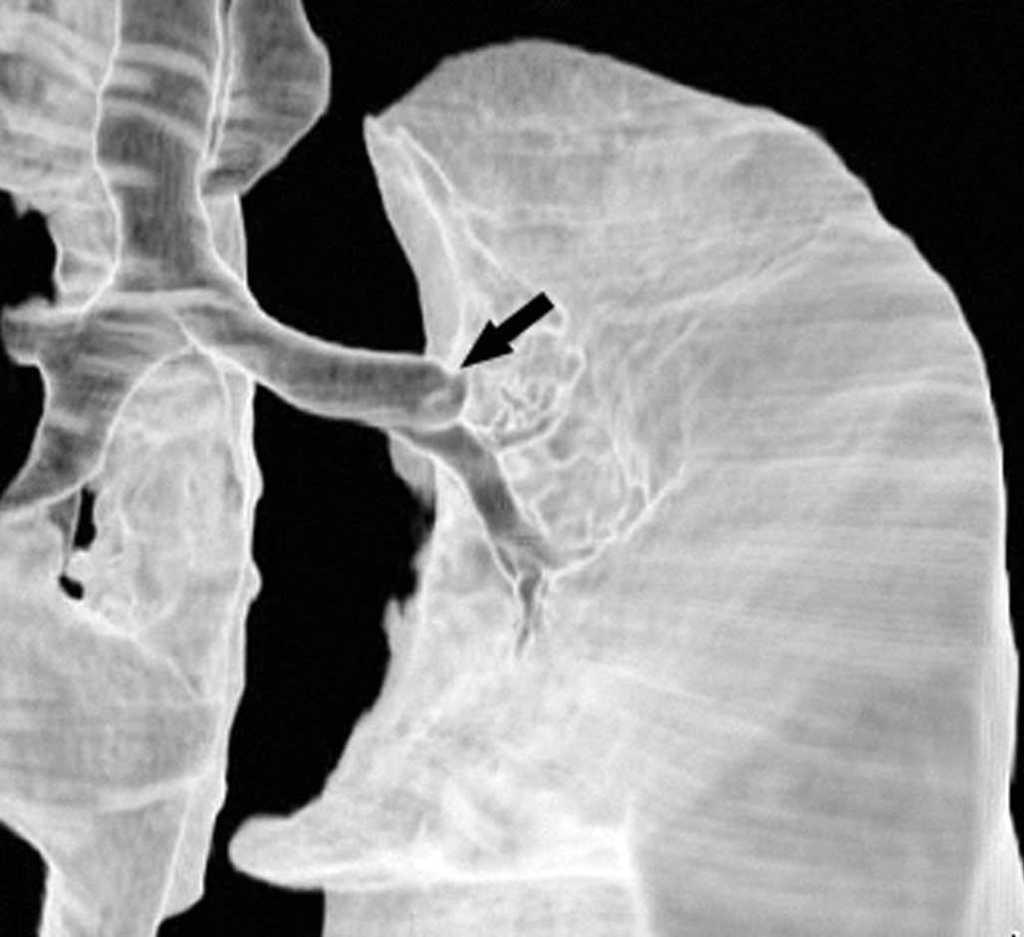

La resonancia magnética (RM) se utiliza principalmente para solventar problemas puntuales, y cada vez se emplea menos dado que la TCMD se ha equiparado con la RM en la capacidad de reconstruir en cualquier plano del espacio. Actualmente, la RM se debe reservar para la evaluación de los tumores del sulcus superior, aunque hay autores que consideran que debe emplearse sólo cuando existe invasión del canal medular, ya que en el resto de las situaciones la TCMD da suficiente información para obviar dicha técnica10 (fig. 10).

Fig. 10.--Tumor del sulcus superior. Tomografía computarizada (TC). (A) TC torácica con contraste, con reconstrucción coronal. Masa cavitada que ocupa todo el segmento apical del lóbulo superior derecho y engloba la arteria lobar superior. (B) En la reconstrucción sagital, se pone de manifiesto la infiltración de la vena cava superior (flecha).